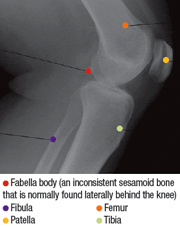

Fig. 6: Lateral view of the knee.

There are three common variants that can seen on this view. The fabella, a common sesamoid bone in the lateral head of the gastrocnemius muscle, occurring in 10 to 30 percent of individuals, is seen on this lateral view of the knee (Fig. 6). The second common variant is the tibial tuberosity, which can appear like an avulsion fracture of the tibial tuberosity. It is sometimes difficult to determine if there is an avulsion fracture or just an unfused apophysis. The epiphyseal region of the tibial head forms a beak-shaped process that extends downward anteriorly over the tibia at its distal end. There is an isolated ossification center which forms the tuberosity.